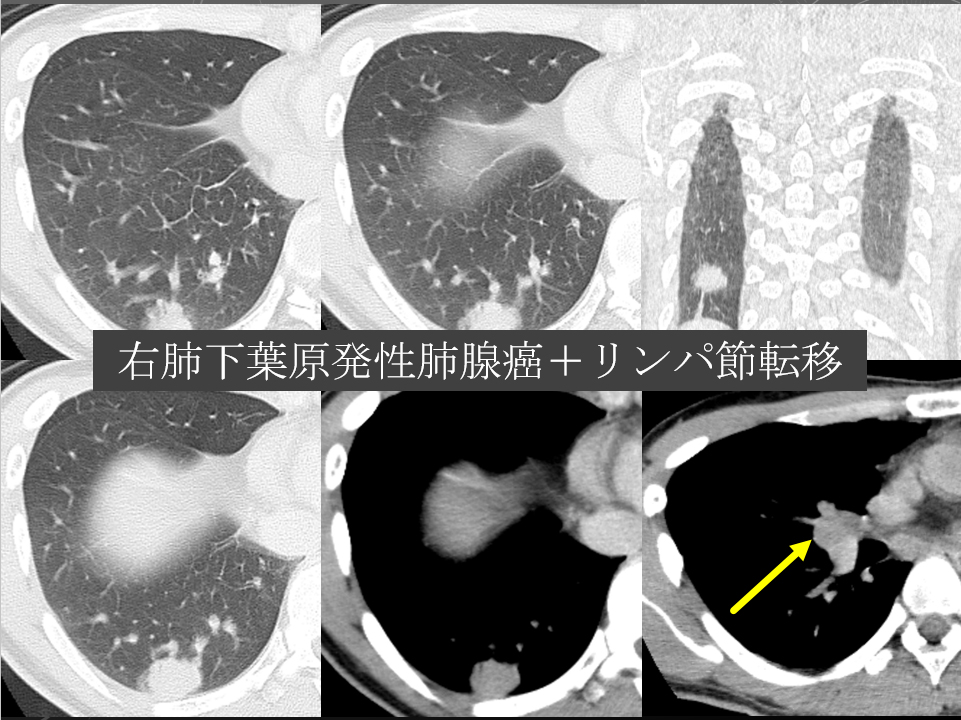

68F CEA 高値精査。消化器内科依頼。既往に脳梗塞、心筋梗塞、胃ポリープあり。

右肺下葉腺癌。

右肺下葉の縦隔側には最大径31mm大の不整形な腫瘤性病変を認めます。表面には部分的にspicula所見が見られ、胸膜に広汎に隣接するように存在しています。内部は辺縁を中心に淡い造影効果を呈しています。原発性肺癌病巣が疑われます。肺門部にはリンパ節腫大像が見られますが、縦隔領域に明らかに有意なリンパ節腫大は指摘出来ません。

左肺下葉に末梢側には淡い濃度上昇所見が見られ、GGO病変が疑われます。この他、肺野に明らかな腫瘤性病変は指摘できません。

右肺下葉原発性肺癌 ( adenocarcinoma )

右肺下葉原発性肺癌 ( adenocarcinoma )